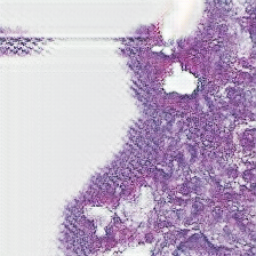

For Target Domain, the MHIST dataset [2] is used (available at https://bmirds.github.io/MHIST/ ), which contains high quality H&E stained histopathology images suitable for learning realistic color and texture distributions.Jana The dataset contains 3,152 H&E images. Some examples are displayed in Figure 1.

The Figure 3 shows virtual H&E generation from light-sheet microscopy image. Each column represents a different type of image. Each row corresponds to a different slice. From these images, it can be observed that the CycleGAN has learned to map the nuclear and cytoplasmic signals to the characteristic H&E colors. Overall tissue morphology and structure are largely preserved, demonstrating that the model captures the spatial relationships of nuclei and cytoplasm from the fluorescence channels.

| C01 | C02 | virtual H&E images |